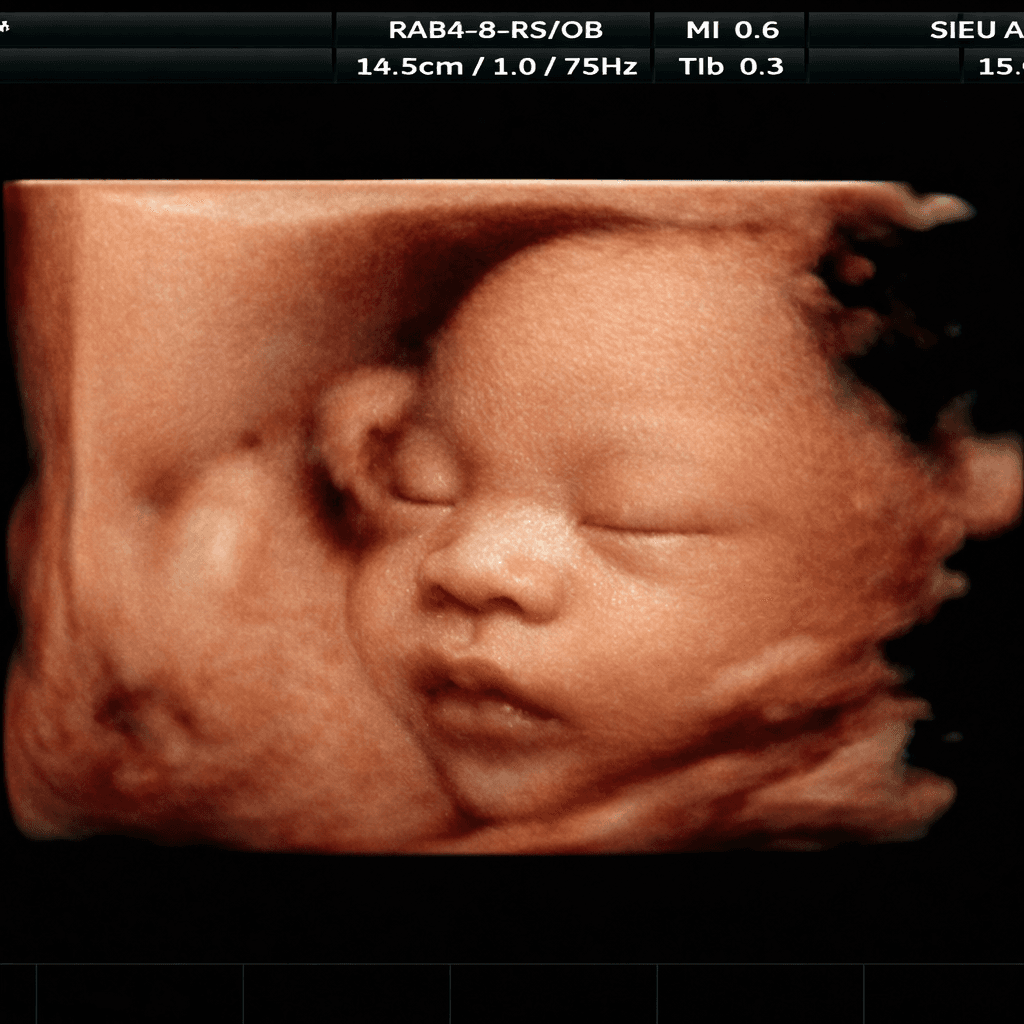

Vuốt để xem sự khác biệt giữa ảnh siêu âm gốc và hình ảnh AI làm nét

Ảnh gốc nhiễu hạt, khó nhìn

Tốn nhiều tiền đi siêu âm 4D/5D nhưng cấu trúc mặt bé vẫn bị móp méo, che khuất bởi nhau thai hoặc nước ối đục.